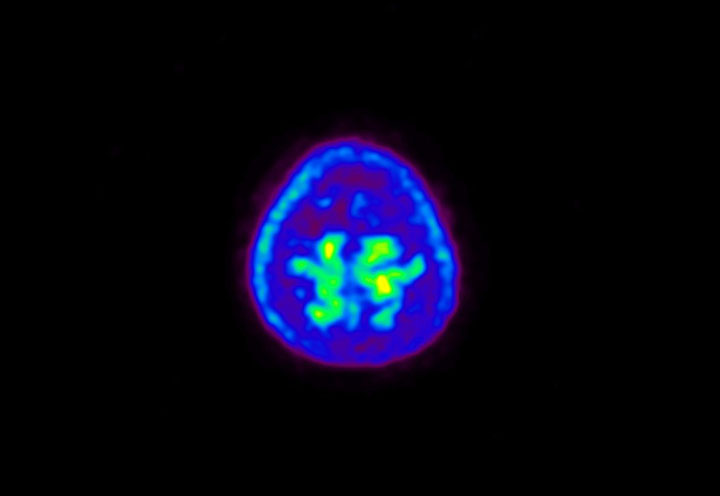

Head / Case5 : Amyloid

Coronal

Courtesy : Kindai University Hospital

- Imaging protocol

- Injected dose: 4.27 MBq/kg, 18F-Flutemetamol

- Uptake time: 99 minutes

- Scan time: 20 minutes